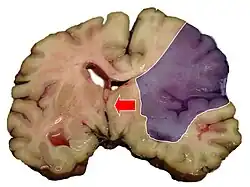

Midline shift is a shift of the brain past its center line.[1] The sign may be evident on neuroimaging such as CT scanning.[1] The sign is considered ominous because it is commonly associated with a distortion of the brain stem that can cause serious dysfunction evidenced by abnormal posturing and failure of the pupils to constrict in response to light.[1] Midline shift is often associated with high intracranial pressure (ICP), which can be deadly.[1] In fact, midline shift is a measure of ICP; presence of the former is an indication of the latter.[2] Presence of midline shift is an indication for neurosurgeons to take measures to monitor and control ICP.[1] Immediate surgery may be indicated when there is a midline shift of over 5 mm.[3][4] The sign can be caused by conditions including traumatic brain injury,[1] stroke, hematoma, or birth deformity that leads to a raised intracranial pressure.

Midline shift measurements and imaging has multiple applications. The severity of brain damage is determined by the magnitude of the change in symmetry. Another use is secondary screening to determine deviations in brain trauma at different times after a traumatic injury as well as initial shifts immediately after.[3] The severity of shift is directly proportional to the likeliness of surgery having to be performed. The degree of MLS can also be used to diagnose the pathology that caused it. The MLS measurement can be used to successfully distinguish between a variety of intracranial conditions including acute subdural hematoma,[5][7] malignant middle cerebral artery infarction,[3] epidural hematoma, subarachnoid hemorrhage, chronic subdural hematoma, infarction, intraventrical hemorrhage, a combination of these symptoms, or the absence of pertinent damage altogether.[7]